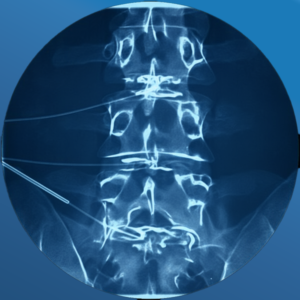

During a Discogram, a physician can identify which disc is causing you discomfort by injecting dye into one or more discs and viewing them on an x-ray or CT scan. The procedure helps doctors know which disk to treat — or sometimes surgically remove.

- Insert a needle into your back and into the center of a disc

- Inject dye into the disc and then remove the needle

After the injections, you might need to have an x-ray or CT scan of your injected discs. If the injected dye has spread from the center of a disc, that means the disc has tears and is damaged.